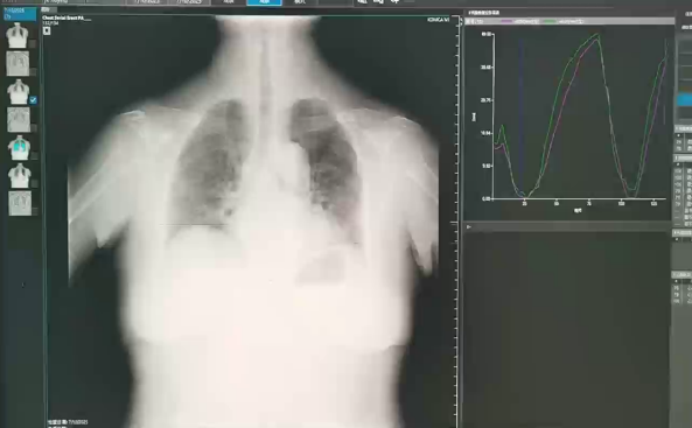

• 胸部正侧位、颈椎动力位+双斜位(图2):两肺间质性肺炎;双侧少量胸腔积液;主动脉硬化;颈椎、胸腰椎退行性变。

图片

2  患者胸部正侧位、颈椎动力位X线片

• 膈肌超声检查:双侧膈肌最大吸气末运动幅度值偏低右侧膈肌增厚率测值约25%;左侧膈肌增厚率测值约29%双侧膈肌厚度测值未见明显异常。(检查中患者难以坚持平卧,紧张焦虑不安)

• 动态胸片下横膈垂直位移图表:平静呼吸时间,两侧膈肌运动曲线平滑,对称,未见锯齿样改变(图3);深呼吸时双侧膈肌活动度严重受限,并伴有锯齿状运动模式(图4)。由此得出结论:患者呼吸运动配合欠佳,双侧膈肌平静呼吸、尽力呼吸位差均小于30 mm,考虑双侧膈肌功能障碍。